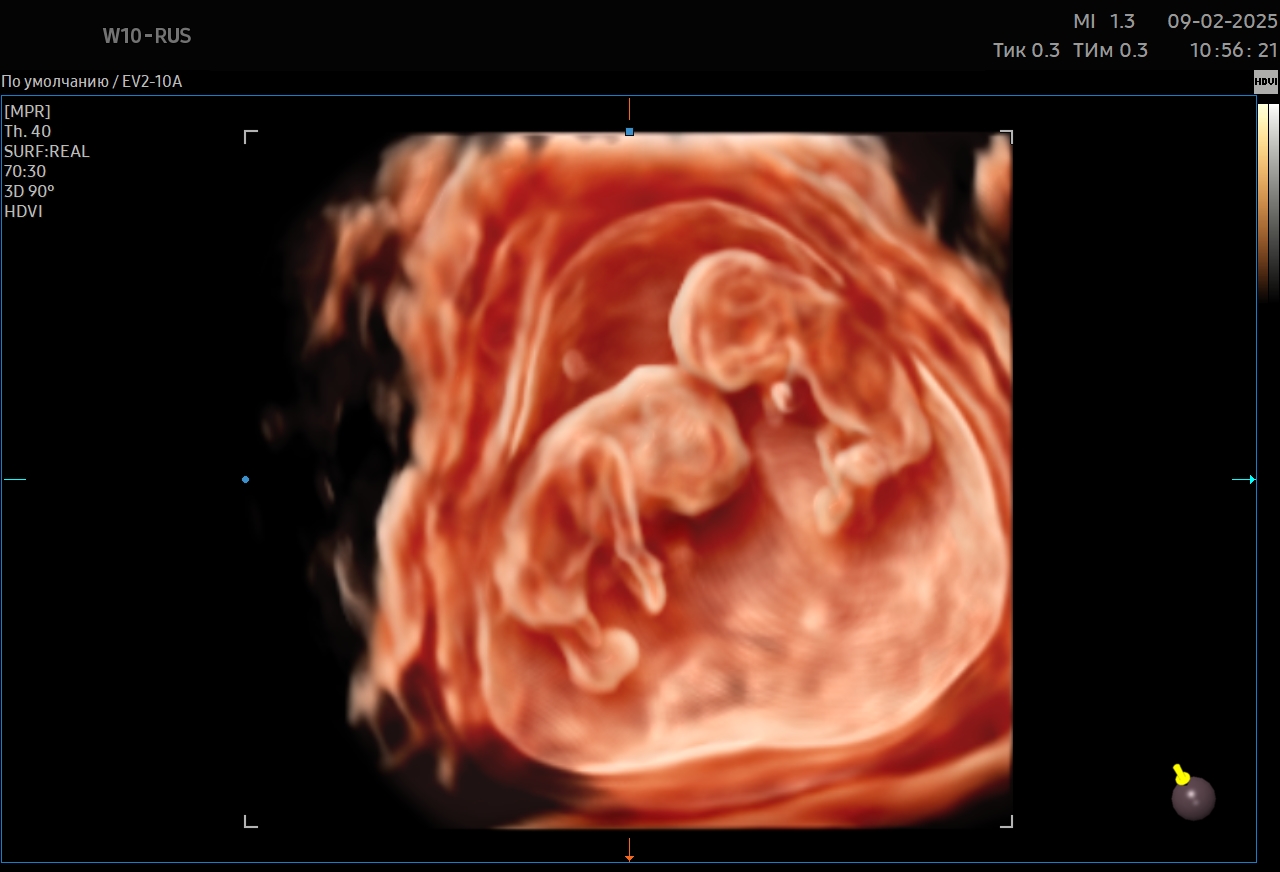

УЗИ при беременности — это неинвазивный и безопасный метод диагностики, позволяющий врачу оценить развитие малыша и состояние будущей мамы на всех этапах вынашивания. Во время исследования специалист детально осматривает анатомию плода, плаценту, околоплодные воды и общую динамику беременности.

• Специалист последовательно осматривает плод, плаценту, околоплодные воды, измеряет необходимые параметры и фиксирует данные.

Результаты известны сразу после завершения УЗИ. Врач подробно рассказывает, как развивается ребенок, что видно в полости матки, какие показатели соответствуют сроку беременности. Пациентка получает письменное заключение с описанием всех параметров. Если возникла необходимость в дополнительной оценке (например, экспертное УЗИ или допплерометрия), специалист объяснит причины и подберет оптимальное время проведения.